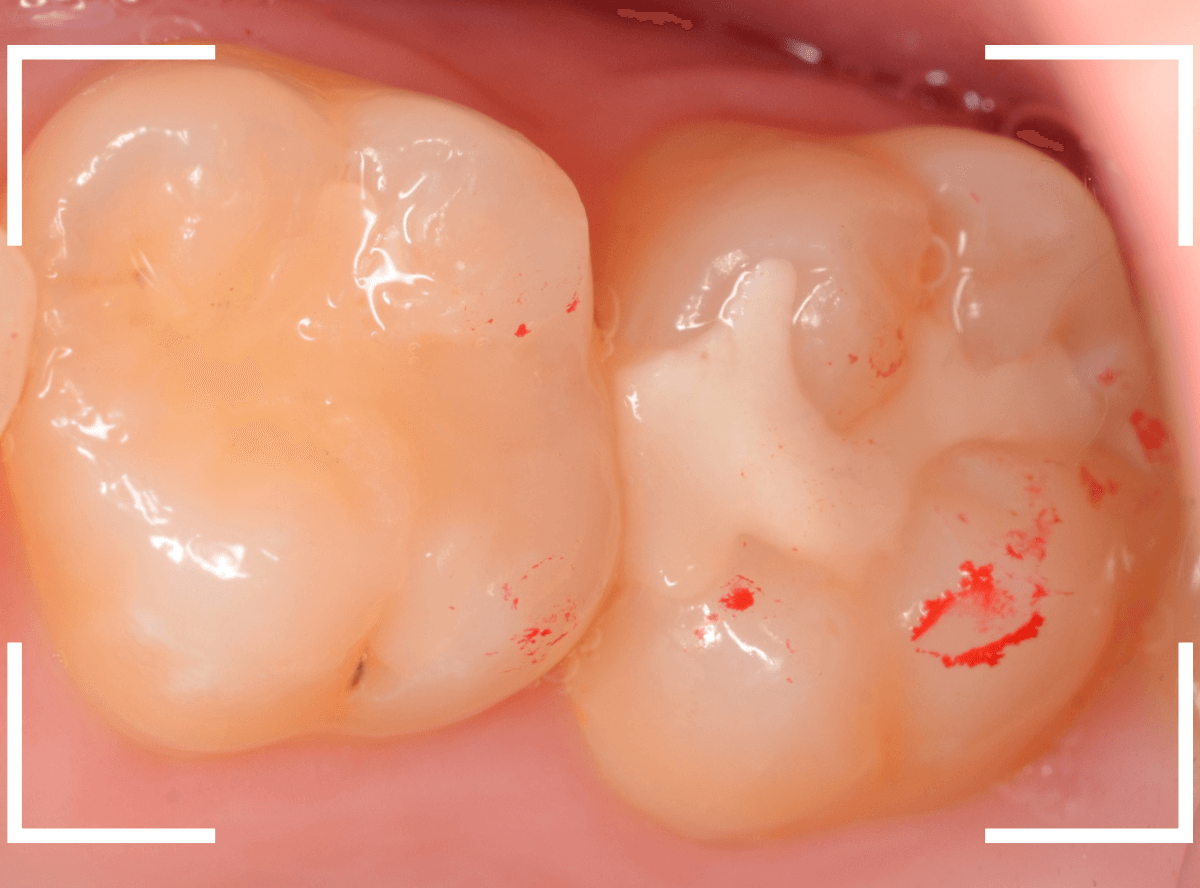

Case.26 4歯連続したセラミック・インレー

4本連続して歯と歯の間の虫歯を治療した患者さんのケースです。

虫歯を再発させないためには、歯と歯のすき間を物がつまらないよう、精密に再製する必要があります。

患者さんのご希望により、セラミック・インレーで修復する事になりました。

模型上で歯と歯のすき間を精密に再現・調整できるのが、セラミック・インレーの大きな利点です。

歯をトリミングして、型を取ります。

模型上で精密に製作します。

最終setした状態です。

左側の大臼歯2本が、ジルコニア・インレー

右側の小臼歯2本が、E-MAX・インレー

になります。

見た目にほとんど遜色ない仕上がりにできました。

普段あまりしない、4歯連続のインレー治療でしたが、精密に仕上げ・setする事が出来てホッとしました。